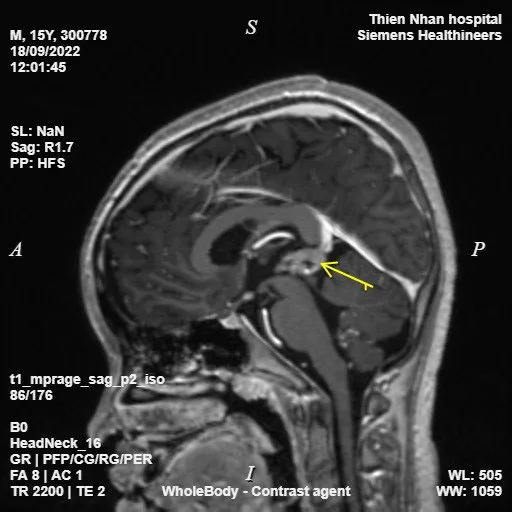

Hình ảnh chụp MRI toàn thân của bệnh nhi cho thấy u tế bào mầm di căn tuyến tùng |

Kết quả chụp MRI tại Thiện Nhân cho thấy khối u di căn nghiêm trọng đến tận vùng đuôi ngựa của tủy sống. Cùng thời điểm, có đoàn chuyên gia Hoa Kỳ về u não trẻ em đến làm việc tại Bệnh viện Phụ Sản - Nhi Đà Nẵng. Từ sự kết nối của Thiện Nhân, các cuộc hội chẩn liên tỉnh giữa các bác sĩ Thiện Nhân, các chuyên gia tại Hà Nội, TPHCM… và đoàn chuyên gia Hoa Kỳ diễn ra liên tục.

Kết luận cuối cùng ghi nhận chẩn đoán của Thiện Nhân là hoàn toàn chính xác, u tế bào mầm tuyến yên đã di căn đến tủy sống, cần được điều trị càng sớm càng tốt. Lập tức, các bác sĩ Thiện Nhân đã họp bàn và tư vấn với gia đình về nơi điều trị cho bệnh nhi. Sau gần 3 tháng với 4 đợt hóa trị, các bác sĩ tại Thiện Nhân nhận được thông báo hiện tại khối u đã không còn sau khi bệnh nhi chụp lại MRI não. Một kết quả đầy hy vọng và hạnh phúc cho em, cho gia đình và đặc biệt là đội ngũ y bác sĩ Thiện Nhân.